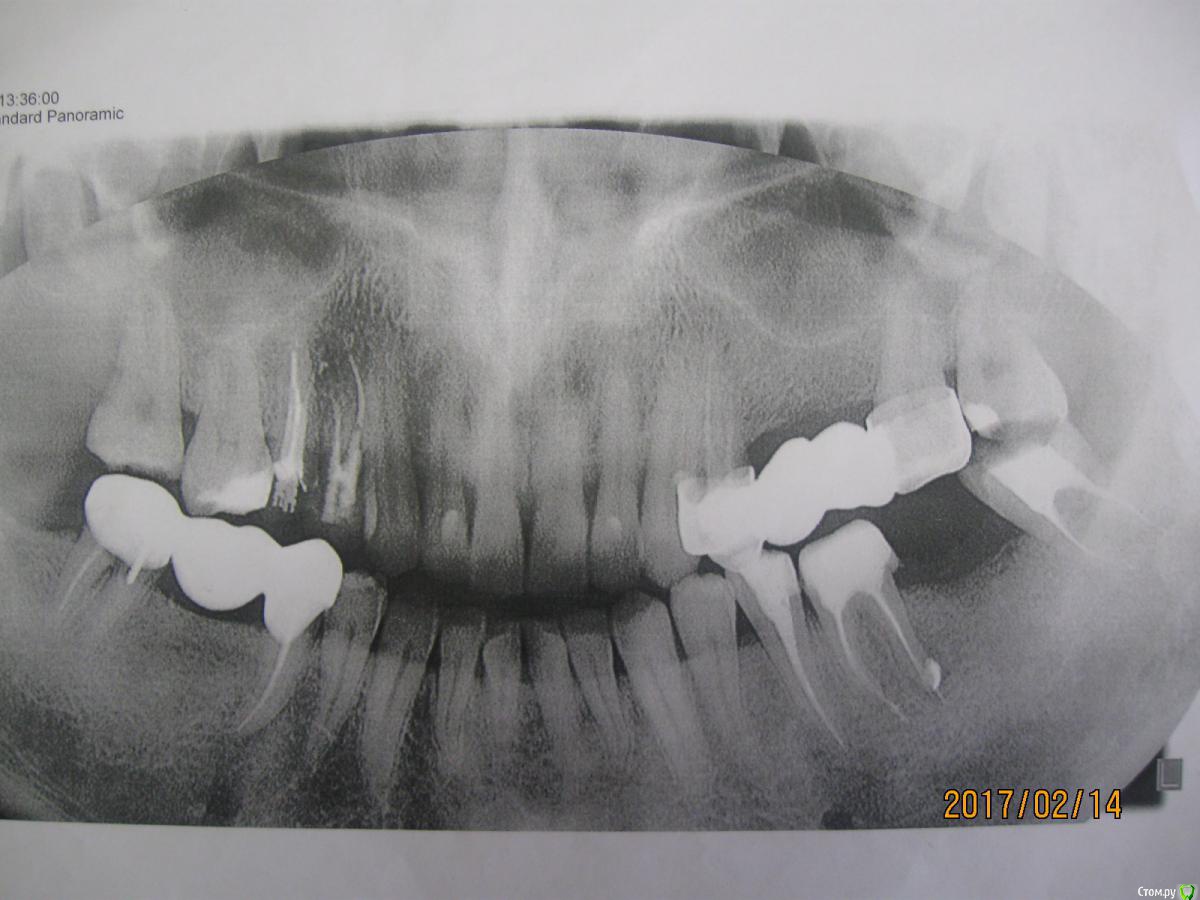

meld Опубликовано 17 февраля, 2017 Поделиться Опубликовано 17 февраля, 2017 (изменено) Здравствуйте! Справа снизу лет 10 назад постановлен мост. Были планы его переделать, т.к. под коронкой на седьмом зубе образовалась щель и под коронкой появилось пустое пространствою. Сделал рентген, в области бифуркации разошлись корни. Терапевт сказала, что если есть твердые ткани, то она зуб восстановит (разделит корни) и отправила на консультацию к ортопеду. Я сходил на консультацию к двум ортопедам. Один говорит, что зуб надо удалять, второй говорит, что корни в хорошем состоянии, просто осела кость и зуб можно спасти и предлагает снять мост и посмотреть, что там. Также я сходил на прием к имплантологу - он предлагает снять мост, удалить седьмой зуб, поставить два импланта - 6 и 7 зубы. К сожалению, денег на два импланта нет, я хочу поставить пока один - 6 зуб. У имплантолога понравилась цена и гарантия - если что-то случится, он переделает бесплатно. Настораживает, что для установки одного импланта он не пользуется хирургическим шаблоном.Зуб под мостом не болит, только иногда ноет, мост не шатается. Второй ортопед говорит, что он может так простоять лет 5-10Поэтому у меня появились вопросы:1. Можно ли спасти седьмой зуб справа снизу2. Критично ли, что имплантолог не пользуется хирургическим шаблоном для установки одного импланта.Спасибо Изменено 17 февраля, 2017 пользователем meld Ссылка на комментарий

Bier Опубликовано 20 февраля, 2017 Поделиться Опубликовано 20 февраля, 2017 7й зуб на удаление, там кариес корня на медиальном корне, в одном дистальном смысла нет. Выброшенные деньги. Ссылка на комментарий